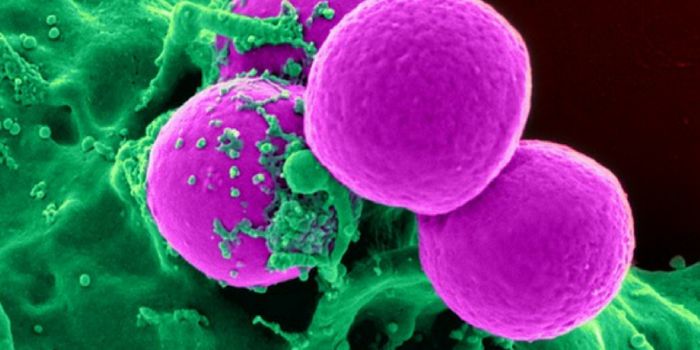

AUG 23, 2017ImmunologyA bacterium called Staphylococcus aureus is arguably one of the world’s most dangerous superbugs. It made The Worl ...